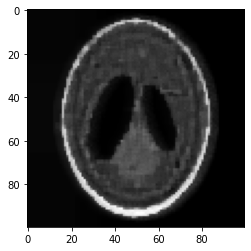

1. Poisson image de-blurring with total variation (TV) regularization [33, 15, 10]. Let the m×n𝑚𝑛m\times n matrix X𝑋X be the true representation of an image, such that each entry Xij0subscript𝑋𝑖𝑗0X_{ij}\geq 0 represents the intensity of the pixel at location (i,j)[m]×[n]𝑖𝑗delimited-[]𝑚delimited-[]𝑛(i,j)\in[m]\times[n], and Xij{0,1,,M}subscript𝑋𝑖𝑗01𝑀X_{ij}\in\{0,1,\ldots,M\}, where M:=2b1assign𝑀superscript2𝑏1M:=2^{b}-1 for b𝑏b-bit images. In many applications, ranging from microscopy to astronomy, we observe a blurred image contaminated by Poisson noise, which we denote by Y𝑌Y, and we wish to estimate the true image X𝑋X from Y𝑌Y. The generative model of Y𝑌Y from X𝑋X is presumed to be as follows. Let 𝖠:m×nm×n:𝖠superscript𝑚𝑛superscript𝑚𝑛\mathsf{A}:\mathbb{R}^{m\times n}\to\mathbb{R}^{m\times n} denote the 2D discrete convolutional (linear) operator with periodic boundary conditions, which is assumed to be known. This convolutional operator is defined by a p×p𝑝𝑝p\times p 2D convolutional kernel with a size q:=p2assign𝑞superscript𝑝2q:=p^{2} that is typically much smaller than the size of image N:=mnassign𝑁𝑚𝑛N:=mn. (For an illustration of the 2D convolution, see [32] for example.) The blurred image Y~~𝑌\widetilde{Y} is obtained by passing X𝑋X through 𝖠𝖠\mathsf{A}, i.e., Y~:=𝖠(X)assign~𝑌𝖠𝑋\widetilde{Y}:=\mathsf{A}(X), and the observed image Y𝑌Y results from adding independent entry-wise Poisson noise to Y~~𝑌\widetilde{Y}, i.e., Yij𝖯𝗈𝗂𝗌𝗌(Y~ij)similar-tosubscript𝑌𝑖𝑗𝖯𝗈𝗂𝗌𝗌subscript~𝑌𝑖𝑗Y_{ij}\sim{\sf Poiss}(\widetilde{Y}_{ij}), for all (i,j)[m]×[n]𝑖𝑗delimited-[]𝑚delimited-[]𝑛(i,j)\in[m]\times[n], and {Yij}(i,j)[m]×[n]subscriptsubscript𝑌𝑖𝑗𝑖𝑗delimited-[]𝑚delimited-[]𝑛\{Y_{ij}\}_{(i,j)\in[m]\times[n]} are assumed to be independent.

is a standard formulation of the total variation. Here we see that (1.5) is an instance of (P)𝑃(P) with f(u):=l=1Nylln(ul)assign𝑓𝑢superscriptsubscript𝑙1𝑁subscript𝑦𝑙subscript𝑢𝑙f(u):=-\textstyle\sum_{l=1}^{N}y_{l}\ln\big{(}u_{l}), 𝒦:=+Nassign𝒦subscriptsuperscript𝑁\mathcal{K}:=\mathbb{R}^{N}_{+}, h(x):=(l=1Nal)x+λTV(x)+ι𝒳assign𝑥superscriptsuperscriptsubscript𝑙1𝑁subscript𝑎𝑙top𝑥𝜆TV𝑥subscript𝜄𝒳h(x):=(\sum_{l=1}^{N}a_{l})^{\top}x+\lambda{\rm TV}(x)+\iota_{\mathcal{X}} where 𝒳={xN:0xMe}𝒳conditional-set𝑥superscript𝑁0𝑥𝑀𝑒\mathcal{X}=\{x\in\mathbb{R}^{N}:0\leq x\leq Me\}, 𝖠𝖠\mathsf{A} is defined by (𝖠x)l:=alxassignsubscript𝖠𝑥𝑙superscriptsubscript𝑎𝑙top𝑥(\mathsf{A}x)_{l}:=a_{l}^{\top}x, l=1,,N𝑙1𝑁l=1,\ldots,N, and θ=l=1Nyl𝜃superscriptsubscript𝑙1𝑁subscript𝑦𝑙\theta=\sum_{l=1}^{N}y_{l}. We note that yl1subscript𝑦𝑙1y_{l}\geq 1 whenever yl0subscript𝑦𝑙0y_{l}\neq 0 for all l[N]𝑙delimited-[]𝑁l\in[N], and hence fθ(𝒦)𝑓subscript𝜃𝒦f\in\mathcal{B}_{\theta}(\mathcal{K}). In Section 4.1 we will discuss how the Frank-Wolfe sub-problem (1.3) associated with (1.5) can be efficiently solved.

We apply our method to the TV-regularized Poisson image de-blurring problem. We present computational experiments that point to the potential usefulness of our generalized Frank-Wolfe method on this imaging problem in Section 4.1.

Outline. The paper is organized as follows. In Section 2 we present and analyze our generalized Frank-Wolfe method for (P)𝑃(P) when fθ(𝒦)𝑓subscript𝜃𝒦f\in\mathcal{B}_{\theta}(\mathcal{K}), using an adaptive step-size strategy that is a natural extension of the strategy developed in [21]. In Section 3 we study the (Fenchel) dual (D)𝐷(D) of (P)𝑃{(P)} and derive and analyze a dual mirror descent method for solving (D)𝐷(D) based on the generalized Frank-Wolfe method for solving (P)𝑃(P). In Section 4 we present computational experiments that point to the potential usefulness of our generalized Frank-Wolfe method on Poisson image de-blurring problems with TV regularization, and we also present computational experiments on the PET problem.